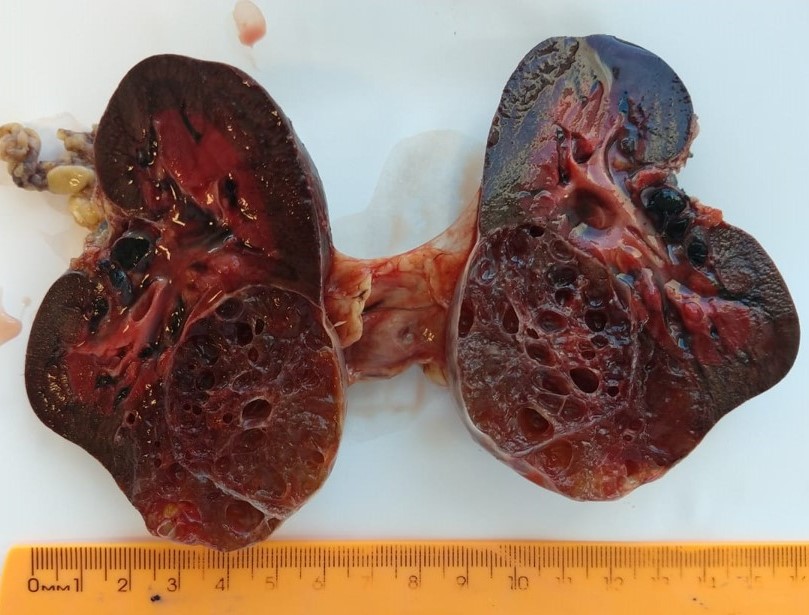

Gross description

- Typically, a large multilocular cystic tumor (mean diameter of 10 cm)

- Thin or variable sized septa

- Well circumscribed

- No expansive nodules

- Reference: J Postgrad Med 2006;52:45

Gross images